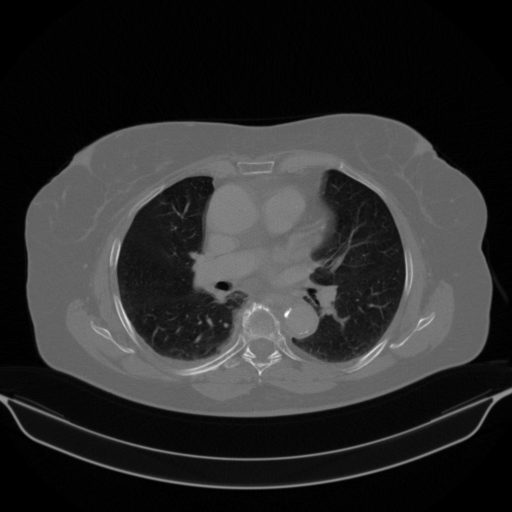

Reconstructed NATIVE CT scan (cycle consistency)

No window - Raw intensity values

Lung window (WL -600, WW 1500 β†’ Low βˆ’1350, High +150)

Mediastinum window (WL 40, WW 400 β†’ Low βˆ’160, High +240)